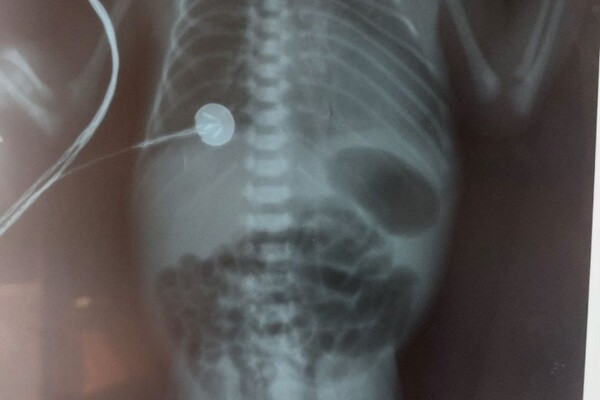

Второй ребенок имел диагноз МВВР с атрезией пищевода (отсутствие части пищевода с разобщенным дистальным и проксимальным сегментом). Он был рожден в очень тяжелом состоянии, с массой тела 1050 грамм. Новорожденные с данным недостатком без оперативного лечения не имеют шансов на жизнь. После дообследования и предоперационной подготовки его прооперировали и сформировали ему новый пищевод. Операция прошла удачно. На сегодняшний день ребенок продолжает свое лечение в отделении реанимации новорожденных.